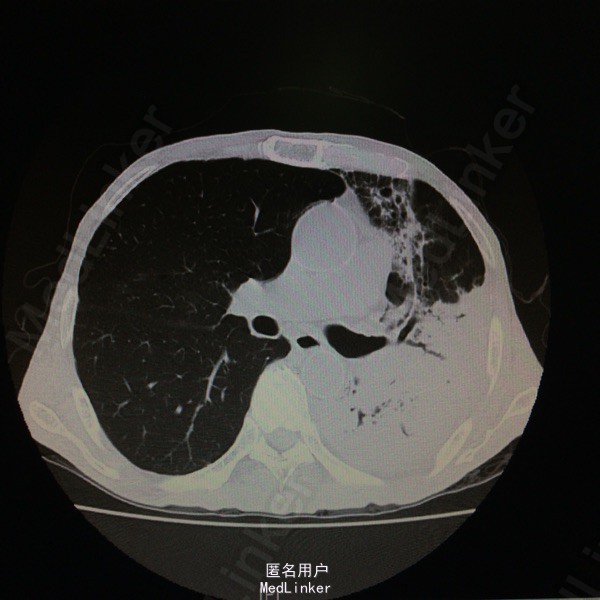

查体:T37.7度,P130次/分,BP 77/59次/分,神情,恶病质,双肺呼吸音粗,未及干湿罗音。 辅助检查:胸部CT示:双肺感染、左肺实变部分坏死。支气管镜示:左上叶气管黏膜感染:真菌?结核?黏膜病理报:符合真菌感染,形态学考虑为曲菌。多次痰培养示:曲霉菌感染。白细胞 12.9*10E9/L,CRP 140ng/ml,ESR 140mm/h,PCT 0.676ng/ml。

随访:患者现予“伏立康唑、两性B”治疗,体温正常,咳嗽咳痰明显好转。复查胸部CT示:左肺上叶病变较前进展,下叶病变较前吸收,左肺实变部分坏死空洞范围较前扩大。 讨论:据痰培养及病理,可明确诊断“肺曲霉菌感染”;予两性霉素B治疗后体温可降至正常,支持该患者发热为曲霉菌感染所致。痰培养及病理结果均支持曲霉菌感染的病例还是少见的。就患者体温变化而言,示治疗有效;其胸部CT示左肺坏死空洞较前扩大,其左肺大部分为坏死组织,空洞会随着这些组织的排出而变大。